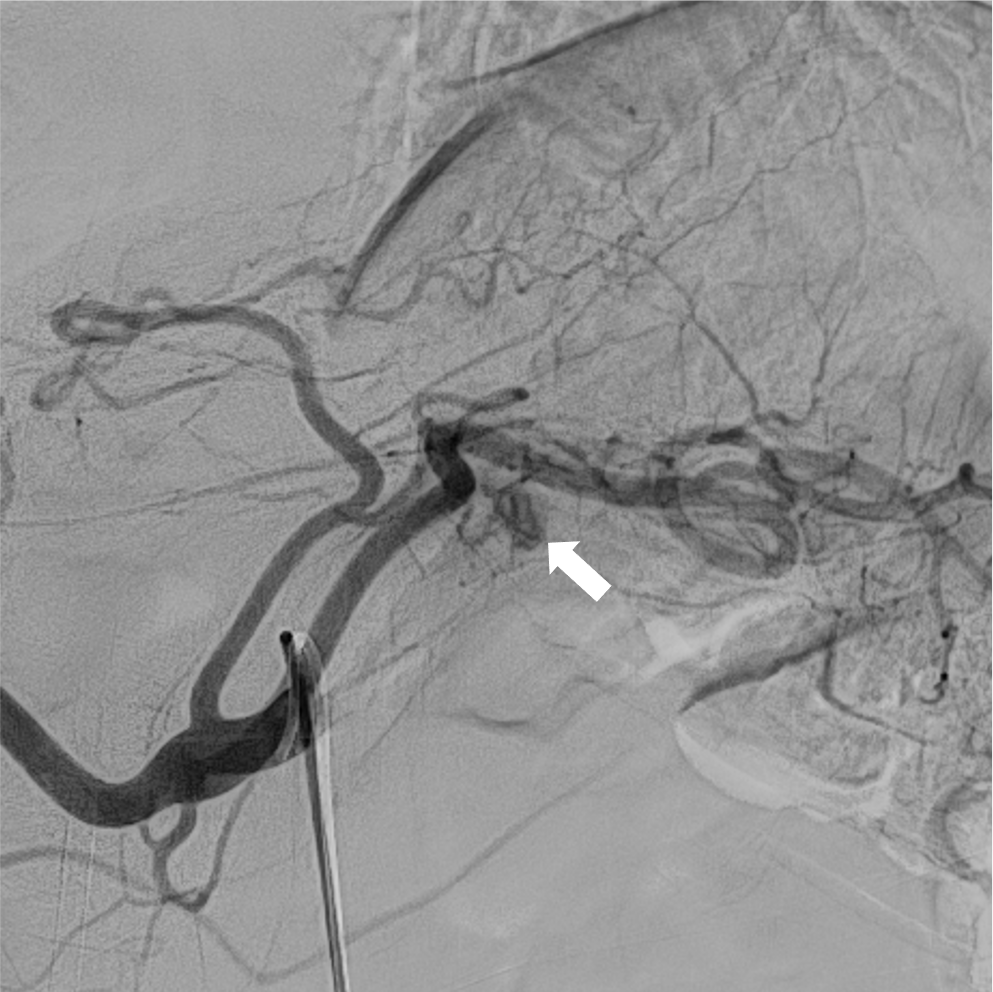

検診で指摘された肺病変のCT精査にて、肺の動静脈奇形(AVM)と診断された。精査および加療目的で当院に紹介され、術前精査のための造影CTを施行した。造影CTにて、膵尾部にAVMを認めた。その後、肺AVMに対するコイル塞栓術が施行され、その際に膵AVMも血管造影にて精査が行われた。膵AVMによる症状はなく経過観察とされ、外来にて定期的にフォローアップされている。

オスラー病(遺伝性出血性毛細血管拡張症、HHT)は、全身の血管に異常を生じる、常染色体優性遺伝の遺伝性疾患であり、特に肺・脳・肝臓・消化管などの動静脈奇形(AVM)や、鼻出血、口・指・鼻などの毛細血管拡張を生じることで知られる。膵臓にも30-60%の患者に血管病変を生じるとされ、その約2/3が毛細血管拡張、約1/3がAVMと言われている。

単純CTでは膵臓の異常血管の描出は困難であり、造影CTは診断において重要である。膵臓のAVMにおいては、(1)拡張・蛇行した供血路、排血路といった異常血管の描出や、(2)動脈相で門脈系の血管の早期造影効果が認められ、診断のポイントとなる。造影CTは血管造影と比較して侵襲性が低く、膵実質の全体の評価にも適しているため、精査のみならず、フォローアップにも用いやすい。